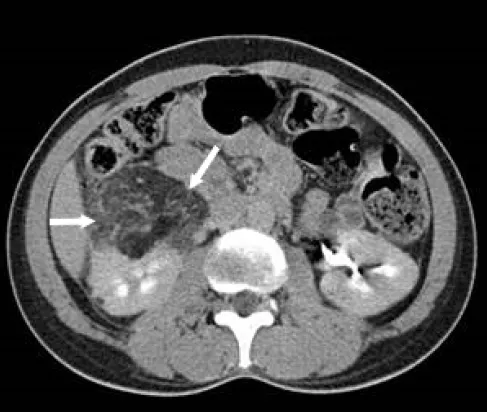

破題關鍵

這題的解題核心在於辨識腎臟腫塊中的脂肪成分,電腦斷層影像中,腎臟腫塊內出現明顯的低密度區域,這是脂肪特有的影像表現,直接指向腎血管肌肉脂肪瘤。